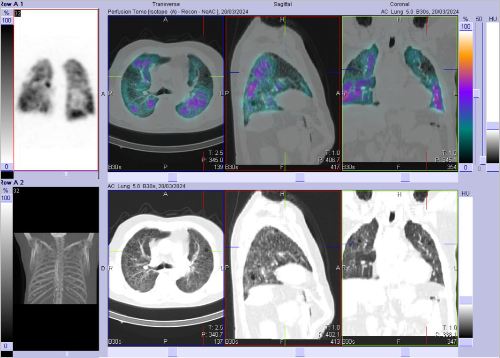

/ Obr. č. 2-7: SPECT/CT plic se zaměřením na vícečetné perfuzní defekty v obou plicních křídlech.

Na scintigramech pozorujeme vícečetné perfuzní defekty v obou plicích (v horním a dolním laloku pravé plíce a v horním a dolním laloku levé plíce). Dále je homogenní distribuce ventilace v obou plicích.

SPECT/CT potvrzuje tyto perfuzní defekty. Na ldCT je dále patrná Vámi popisovaná nespecifická intersticiální pneumonie, taktéž emfyzém, to však nevysvětluje diskrepanci mezi perfuzí a ventilací. Jde tedy o tzv. V/P mismatch.

Závěr: vícečetné perfuzní defekty v obou plicích (v horním a dolním laloku pravé plíce a v horním a dolním laloku levé plíce). Homogenní distribuce ventilace v obou plicích. V/P mismatch.

Relativní distribuce perfuze: L:P 40:60 %, relativní distribuce ventilace L:P 44:56 %.

Nález svědčí pro plicní embolizaci do obou plicních křídel.